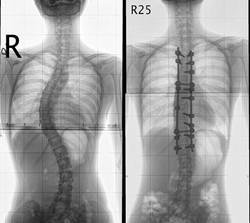

(图:桑先生女士检查时的x光片)

杜爱华主任对桑先生进行检查,发现桑先生由于没有及时进行治疗检查,强直性脊柱炎已经到了非常严重的地步,检查结果显示:胸廓扩张度2.5cm;右足背轻度可凹性浮肿;骶髂关节压痛(+);腰椎侧弯、骶髋关节炎,舌体肥胖、薄黄苔,“4”字试验(+)。王主任根据患者病情为她制定了合适的治疗方案。